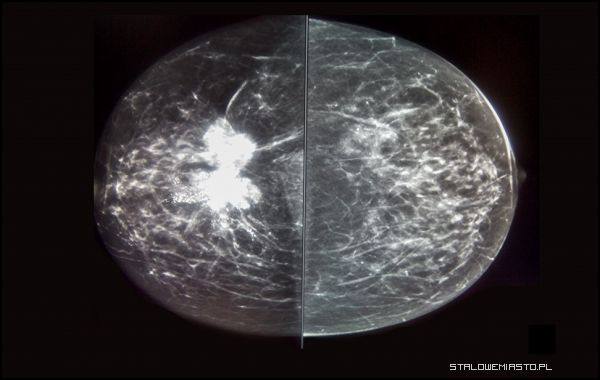

Mammografia uznawana jest za podstawową metodę badania przesiewowego gruczołu piersiowego. Dzięki temu badaniu możliwe jest wykrycie raka piersi w pierwszym stadium. Wykorzystywana jest niewielka dawka promieniowania rentgenowskiego co powoduje, że badanie jest bezpieczne dla pacjentki. Szpital Specjalistyczny SANUS posiada jeden z najnowocześniejszych sprzętów na świecie do wykonywania mammografii, mammografii spektralnej oraz mammografii z tomosyntezą.

- Jest to aparat w pełni cyfrowy, podnoszący poziom diagnostyki do poziomu światowego. Nie jest to zwykły mammograf. Dzisiaj tych mammografów jest bardzo wiele. Są mammografy stacjonarne, są tzw. konwencjonalne, pracujące na zwykłych filmach, są aparaty półcyfrowe. Ten, którym my dysponujemy to jest tzw. pełna cyfra, czyli aparat, który odczytuje na specjalnych czytnikach obraz wywołany za pomocą promieni rentgenowskich. Ten aparat ma przewagę nad innymi, bo obraz nie jest niszczony gdzieś po drodze, czyli nie zarysujemy filmu, nie użyjemy nieprawidłowych odczynników, nie zniekształcimy odczytu temperaturą. Te wszystkie czynniki znikają, jest tylko czysty przesył na kablu. Rozdzielczość matryc, które mamy w aparatach to 5 mln pikseli. Nie ma nic dokładniejszego. Ten aparat potrafi wykryć zmiany 0,1 milimetra. To jest kosmos- przekonuje specjalista radiodiagnostyki Krzysztof Antonowicz.

Jest to najdokładniejsza metoda diagnozowania raka piersi. Badanie to z największą precyzją obrazuje wewnętrzną, warstwową strukturę piersi pacjentek, rozpoznaje nawet najmniejsze nieprawidłowości. Metoda ta o 40% zwiększa wykrywalność raka oraz lepiej obrazuje złośliwe zmiany w piersiach kobiety. Pierś układana jest pod różnym kątem i prześwietlana milimetr po milimetrze. W ten sposób do analizy przekazywane jest około 400 zdjęć 3D. Istnieje możliwość wykrycia najmniejszych zmian, które mogą świadczyć o naturalnym procesie metabolicznym lub być sygnałem zmian nowotworowych.